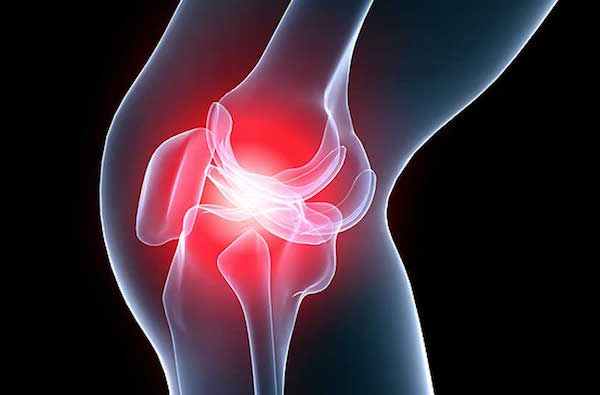

Это воспаление сухожилия с последующим дегенеративным процессом, которое локализуется в области коленного сустава. Патология часто встречается у спортсменов. В большинстве случаев поражается собственная связка надколенника в месте ее крепления к костным структурам.

При пальпации пораженного сухожилия, надколенника ощущается болезненность. Сочленение отекает, объем движений ограничен.

Со временем прогрессирует дегенерация тканей сухожилия, оно истончается, теряет эластичность. Возможен разрыв этой анатомической структуры.

г) Пальпация поднадколенниковой связки (сухожилия надколенника). Пропальпируйте тяж, идущий от внутренней нижней поверхности надколенника до бугристости большеберцовой кости. Инфрапателлярное жировое тело расположено непосредственно позади связки, его пальпация может быть болезненной. При воспалении жирового тела образуется распространенный выпот (рис. 6). Болезненность сухожилия может быть вызвана тендинитом связки надколенника (коленный сустав прыгуна), который развивается в результате перегрузок.

«Колено прыгуна». Это воспаление сухожилия четырехглавой мышцы бедра в месте ее прикрепления к верхнему полюсу надколенника. Также изменения, характерные для «колена прыгуна» могут возникать в точке прикрепления собственной связки надколенника к бугристости большеберцовой кости ниже надколенника.

Причиной заболевания является острая или хроническая профессиональная, спортивная перегрузка. «Колено прыгуна» чаще наблюдается у легкоатлетов, волейболистов, баскетболистов, футболистов. Фактор риска – многократные прыжки на твердой поверхности, форсированное разгибание колена. Стрессовые перегрузки возникают и при спорте выходного дня, многих видах бытовой деятельности (перенос тяжестей, ремонт, уборка).

У пожилых пациентов развитие болей в колене происходит на фоне обычной повседневной деятельности. Клинически отмечается локальная болезненность спереди колена у верхнего или нижнего полюса надколенника. Боль в колене усиливается при разгибании колена, ходьбе по лестнице как вверх, так и вниз, вставании из положения сидя. Приседание на корточки очень болезненно. Боль усиливается при выжимании педалей автомобиля, что затрудняет вождение. Боль нередко усиливается при длительном сидении, что заставляет людей вставать и искать более удобное положение для ноги.

При прощупывании пораженное сухожилие резко болезненно. В переднем отделе коленного сустава в проекции надколенника и его собственной связки можно обнаружить небольшую припухлость. При спортивной травме необходимо прекратить тренировку, зафиксировать коленный сустав и сразу обратиться за медицинской помощью.